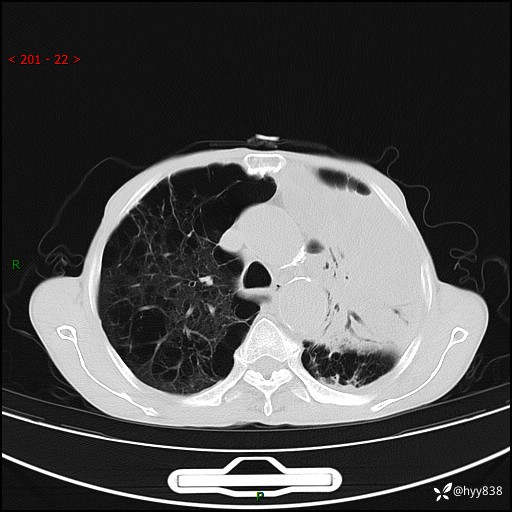

老年男性,反复咳嗽、咳痰、气喘10余年,再发3天。大叶性实变+胸膜病变-结果公布

胸部CT平扫+增强